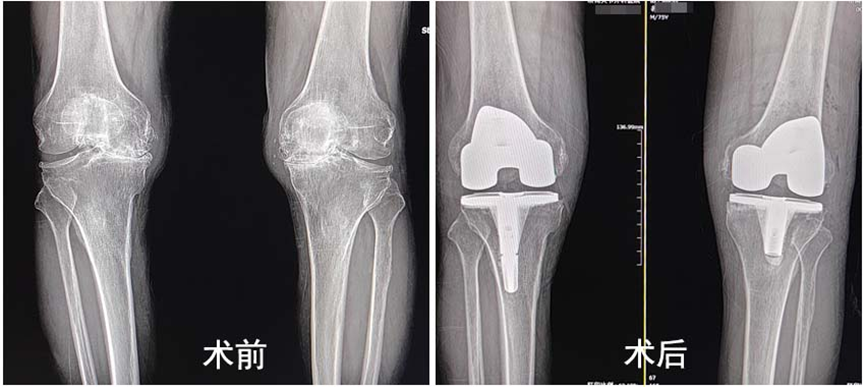

为了不给儿女增添负担,恢复行走能力,好好享受晚年生活,2024年祝大爷经同村病友介绍,前往济南关节外科医院治疗。经医院专家会诊,祝大爷符合手术指征,遂决定为其实施双侧全膝关节置换手术。考虑到祝大爷年纪偏大,基础疾病多,医生决定置换手术分两次进行,先做较为严重的右腿,康复后再置换左腿。

在医生团队的默契配合下,不到一个小时顺利完成了右侧膝关节置换手术。术后祝大爷明显感觉自己的关节功能得到恢复,原本弯曲变形的膝关节变直了,在康复师的帮助下,祝大爷积极进行康复锻炼,术后第一天成功下地行走,术后三天康复出院。经过一年的恢复,祝大爷又进行了左侧的全膝关节置换,恢复良好。